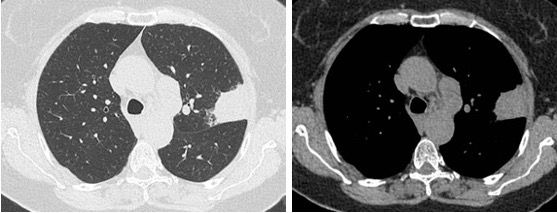

In an asymptomatic 77-year-old woman, former 55 pack-years smoker, a routine X-ray showed a 45-mm superior left lobe lesion (Figure 1). A chest CT scan confirmed a 36-mm superior left lobe lesion and an aortic-pulmonary lymph node enlargement measuring 42 mm, suspicious for neoplasia (Figure 2). A PET-CT scan showed an elevated uptake in the primary lesion, in the aortic-pulmonary lymph node, and in the left hilar lymph node with a standardized uptake value – 40 and 4.3, respectively (Figure 3).

Figure 2. CT scan with pulmonary lesion and mediastinal lymph node.